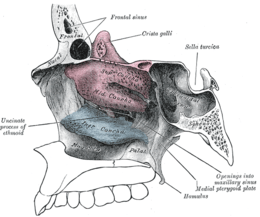

Empty nose syndrome (ENS) is a rare clinical syndrome in which people who have clear nasal passages experience a range of symptoms, most commonly feelings of nasal obstruction, nasal dryness and crusting, and a sensation of being unable to breathe.[1] People who experience ENS have usually undergone a turbinectomy (removal or reduction of turbinates, structures inside the nose) or other surgical procedures that interfere with turbinates; the overall incidence is unknown but it appears to occur in a small percentage of those who undergo nasosinal procedures.[1][2] It appears to be a health care caused condition but its existence as a medical condition, cause, diagnosis and management are controversial.[1] No one disputes that people with the symptoms suffer a great deal.[1][2][3]

Four types have been proposed:[1]

- ENS secondary to inferior turbinate resection

- ENS secondary to middle turbinate resection

- ENS secondary to both inferior and middle turbinate

- ENS after turbinate-sparing procedures

There are no objective physical examination findings that definitely diagnose ENS.[1] Generally, one or more turbinates may be reduced or absent when viewed in medical imaging or via endoscope with no sign of physical obstruction, the mucosa will be dry and pale, and there may be signs of secondary infection.[1]

The cause may be changes to the mucous membrane of nose and to the nerve endings in the mucosa caused by chronic changes to the temperature and humidity of the air flowing inside the nose, caused in turn by removal or reduction of the turbinates.[1][2] The cause may be direct damage to the nerves caused by surgery, but because as of 2015 there was no technology that allowed mapping of the sensory nerves in the nose it has been difficult to determine if this is a cause.[1] Because the occurrence of ENS is rare and investigators have been unable to identify consistent diagnostic features or precipitating features, psychological causes leading to a psychosomatic condition have been proposed.[1][3][4][6]